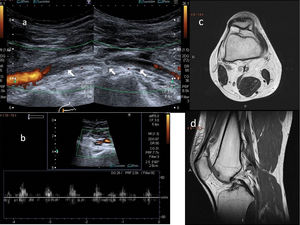

Doppler ultrasound is used as a screening method, as it is non-invasive and does not emit radiation. Examination of the PA starts above the knee joint until it bifurcates bilaterally. The examination is performed with the patient in prone decubitus, with the leg extended and in a neutral position to determine the changes in the vessel intima and the presence of stenosis or aneurysms, as well as the velocity and shape of the spectral curve.16,18 The second part of the examination consists of stress manoeuvres, in which the ankle is placed in dorsiflexion and plantar flexion for up to 30 seconds; the radiologist may aid in maintaining the posture by applying pressure (Fig. 9A). Next, the patient will stand on tiptoe.15,16 At this point, blood flow all along the path of the PA will be evaluated and the presence or absence of blood flow and the decrease in the systolic peak will be determined using stress manoeuvres (Fig. 9B). The dorsalis pedis artery and the posterior tibial artery can also be assessed.17,19

Stress manoeuvres for assessing popliteal artery entrapment syndrome. Patient in prone decubitus, with the leg extended and the ankle in dorsiflexion (A) and plantar extension (B) for 30 seconds. The radiologist can help to maintain the posture by applying pressure. The presence or absence of or changes in blood flow will be evaluated all along the path of the popliteal artery with changes in position. C and D show normal findings on spectral Doppler ultrasound with flexion and extension stress manoeuvres.

Turbulent flow with aliasing is necessary for detecting haemodynamically significant stenosis. Vessel obstruction is considered to be present if blood flow is detected by neither colour nor pulsed-wave Doppler ultrasound18 (Fig. 10). For proper visualisation of anatomical variants, the examination can be supplemented with MR angiography.

A and B) Doppler ultrasound. Subocclusion of the popliteal artery with very weak blood flow in a young patient with popliteal artery entrapment syndrome and signs and symptoms of intermittent claudication. C and D) Non–contrast-enhanced magnetic resonance imaging, axial and sagittal projections, respectively. Abnormal insertion of the medial gastrocnemius muscle, the tendon of which ascends more than normal, passing between the popliteal artery and vein and inserting in the posterior cortex of the femoral metaphysis, where a benign bony outgrowth has formed. Modified Love and Whelan II classification.